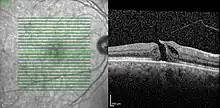

| Optical coherence tomography (OCT) of a macular hole (right) as compared to a normal macula. | |

A macular hole is a small break in the macula, located in the center of the eye's light-sensitive tissue called the retina.